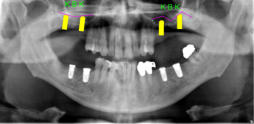

Beispiele für komplexe implantologische Versorgungen aus unserer Gemeinschaftspraxis

(Planung / Endversorgung -- als Röntgenaufnahmen)